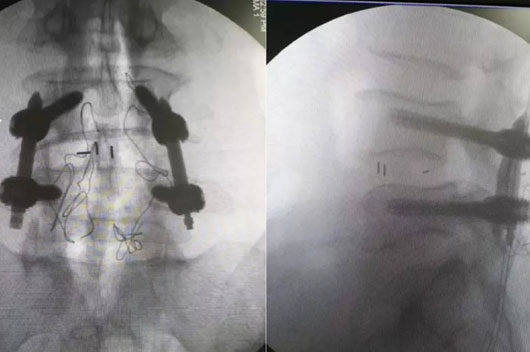

µÚÈý²½£ºÒ½ÉúÑØ×ÅÌ×Ͳ×êÈë·öÒýÕ룬£¬£¬£¬£¬£¬£¬£¬È·ÈÏλÖÃÎÞÎóºó£¬£¬£¬£¬£¬£¬£¬£¬ÔÙ°ÑÖ±¾¶6.5ºÁÃ׵ĿÕÐÄ×µ¹­¸ùÂݶ¤Í¨¹ý·öÒýÕëÀο¿£¬£¬£¬£¬£¬£¬£¬£¬°Î³öµ¼Õë¡£¡£ ¡£¡£¡£¡£ ¡££¨Í¼Îª½­ËÕÊ¡ÈËÃñÒ½Ôº¼¹ÖùÍâ¿ÆÖ÷ÈÎÒó¹úÓ½ÌÊÚÖÃÈë·öÒýÕë¡¢Öö¤£©

µÚËIJ½£ºÒ½Éú¶Ô»¼ÕßÔٴξÙÐÐɨÃ裬£¬£¬£¬£¬£¬£¬£¬È·ÈÏÂݶ¤µÄ¾«×¼Ò»Ö¡£¡£ ¡£¡£¡£¡£ ¡£